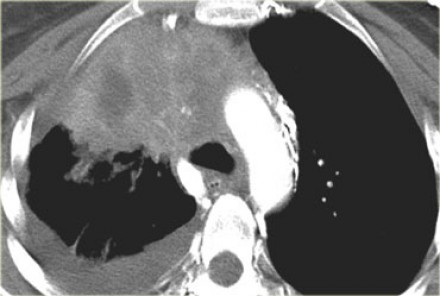

На Т1-изображениях представлен пациент с раком Панкоста Т3-стадии в связи с тем, что поражены корешки только Th1, Th2